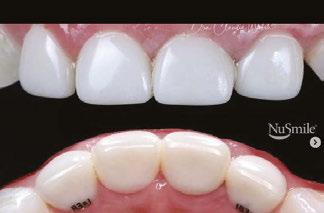

Beyond esthetics: Dr. Patrick Ruck discusses NuSmile® ZR Anterior Crowns as a long-term solution for complex pediatric dental cases

2: NuSmile® Anterior Zirconia crowns at 2-year follow up. Note the high amount of plaque accumulations along the untreated cuspid and existing stainless-steel crowns

This review discusses three clinical cases in which NuSmile® ZR (NuSmile, Houston, Texas) anterior pediatric zirconia crowns were the correct clinical decision in varying clinical scenarios.

around these clinical sites. His anterior zirconia crowns showed healthy gingival margins with little-to-no plaque accumulations. This positive clinical finding is from the highly polished nature and biocompatibility of pediatric zirconia crowns. These restoration features limit plaque accumulations on the restoration and along the marginal gingiva, providing a localized positive aspect directly related to the choice of restorative material (Figure 2).

Figure 3: NuSmile® ZR Crowns were selected as a cementable full coverage restoration. At 6-month recall, apical tissues were healed with excellent gingival health Figure 4: SMART style restorations that were definitively restored with NuSmile® ZR Crowns as an esthetic option to cover SDF staining